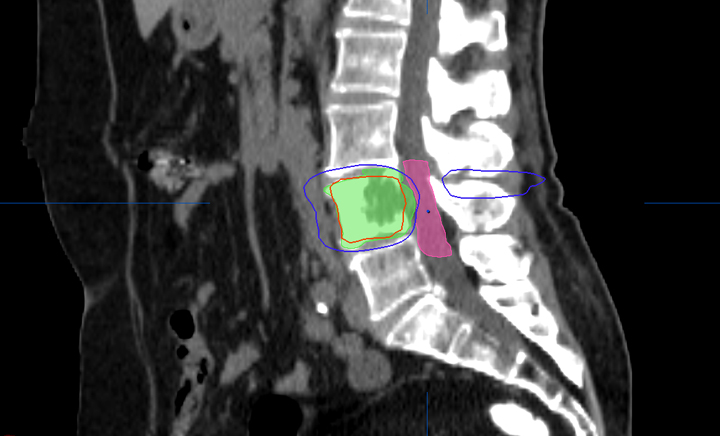

Radioterapia en las metástasis óseas

El 40% de los pacientes tuvo reducción del dolor y mejor calidad de vida a los 10 días de iniciar el tratamiento. Se debe ofrecer radioterapia para las metástasis óseas a todos los pacientes, incluso a aquellos con una supervivencia pobre. JAMA Oncology, 9 de febrero de 2017